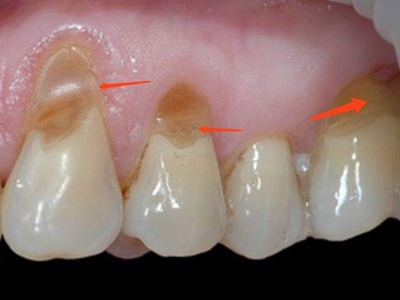

楔状缺损是一种非龋性牙颈部慢性损伤,是指发生在牙齿唇、颊面颈部的慢性硬组织缺损。典型缺损由两个夹面组成,口大底小,呈楔形。楔状缺损多发生于中老年人,主要原因是刷牙不当,防治措施是调整咬合关系,改善刷牙方法,配合相应的治疗。

楔状缺损与年龄相关,即年龄越大,缺损越重,患者多有横刷牙习惯,患牙为多颗甚至全口,常以口角附近的牙齿(尖牙、前磨牙)为重。典型表现为牙颈部缺损,呈楔形,由两个夹面组成,口大底小,缺损处质地坚硬,表面光滑,边缘整齐,无染色,轻微泛黄常为牙齿本色,严重时可导致牙髓腔暴露甚至牙齿横向折断,根据缺损深浅不同,可伴有牙齿敏感甚至疼痛。